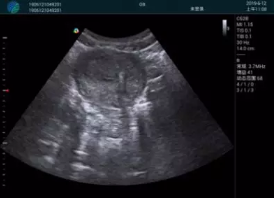

清晰顯示孕囊,通過軟件包計(jì)算孕齡7w+6d

M20實(shí)時引導(dǎo),術(shù)中清晰顯示孕囊被破壞和抽吸針的過程,清晰顯示吸引針

抽吸結(jié)束后縱切子宮,孕囊已被完全抽吸,未見明顯殘留

橫切子宮,發(fā)現(xiàn)右側(cè)宮腔靠近宮角處有少許脫模樣殘留

M20引導(dǎo)下,抽吸針找到右側(cè)宮角處再次清掃

二次抽吸后再次進(jìn)行超聲檢查,宮腔未見殘留,宮腔線清晰顯示